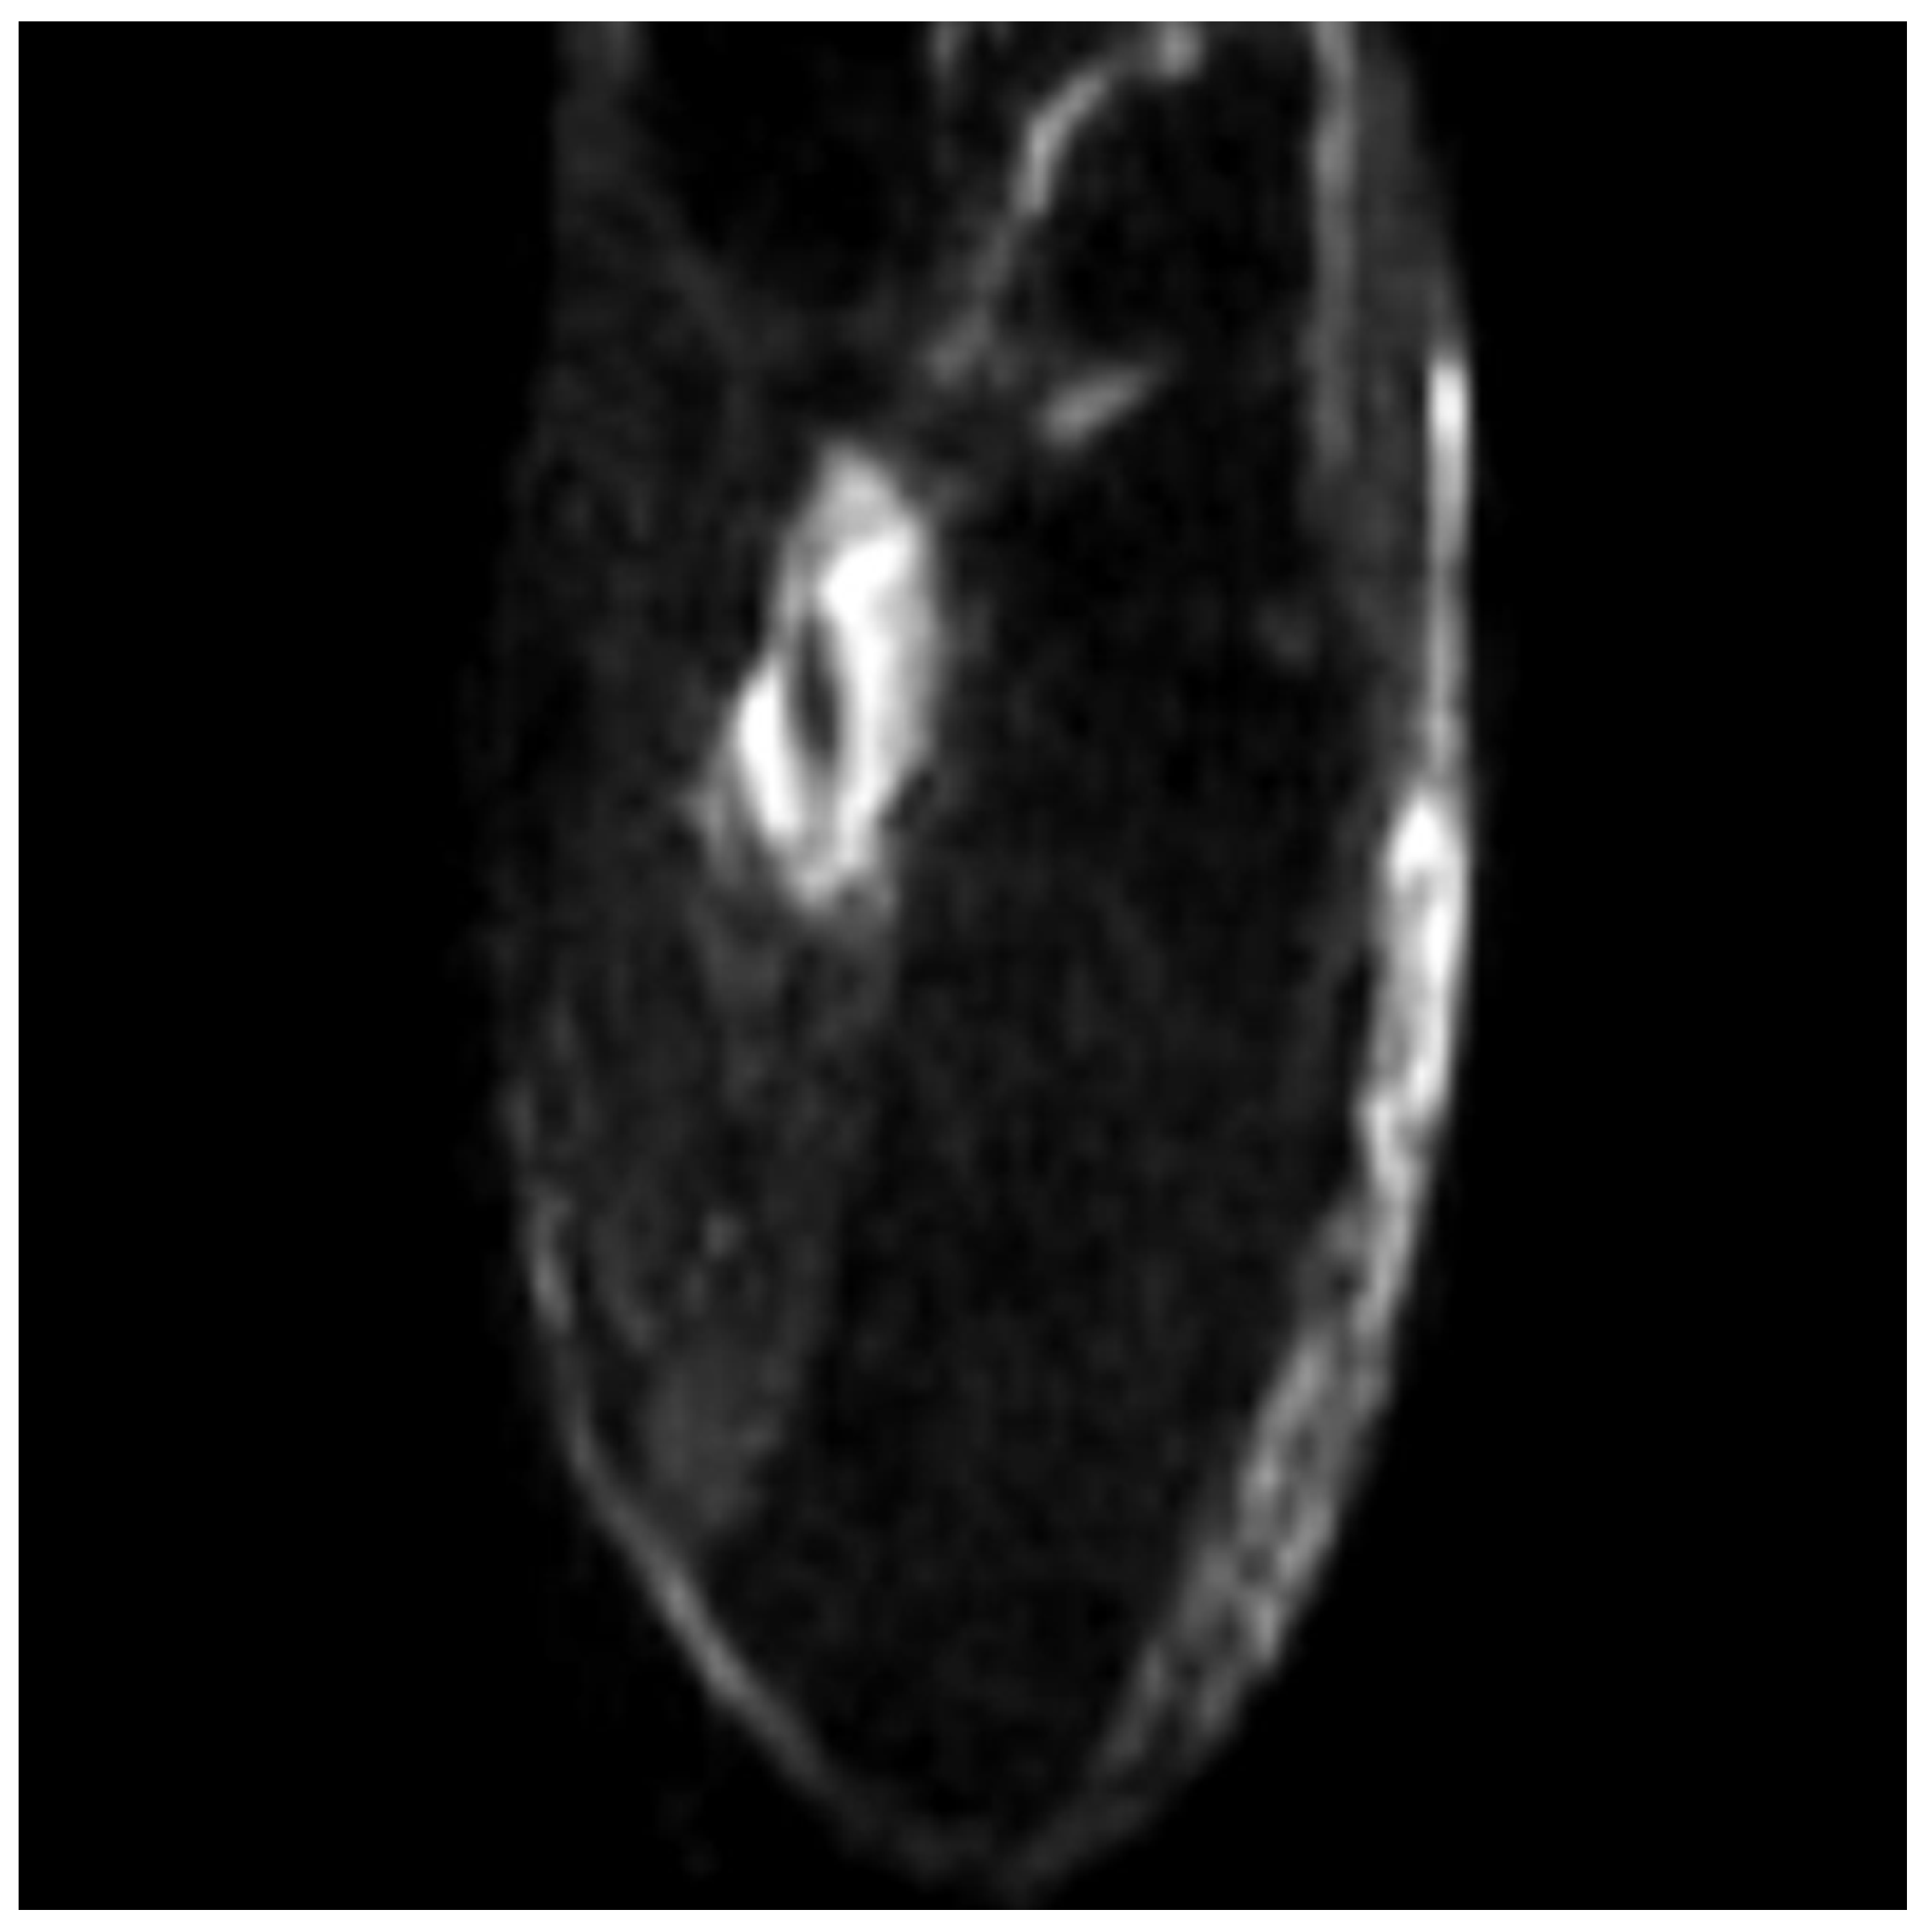

Figure 4.

Axial ADC-DWI presents a TP tendon tear.